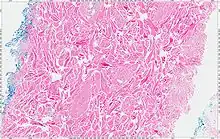

The tumors are unencapsulated and poorly circumscribed, showing a firm, white cut surface. Most tumors are about 3.5 cm, but can be up to 8 cm.[1] By microscopic examination, there are haphazardly arranged thick collagen fibers, with a low cellularity and no pleomorphism. There are usually entrapped fat cells, skeletal muscle, and peripheral nerves. The may be perineural fibrosis. The elastic fibers may be altered, which is why an elastofibroma is considered in the differential diagnosis.[1]